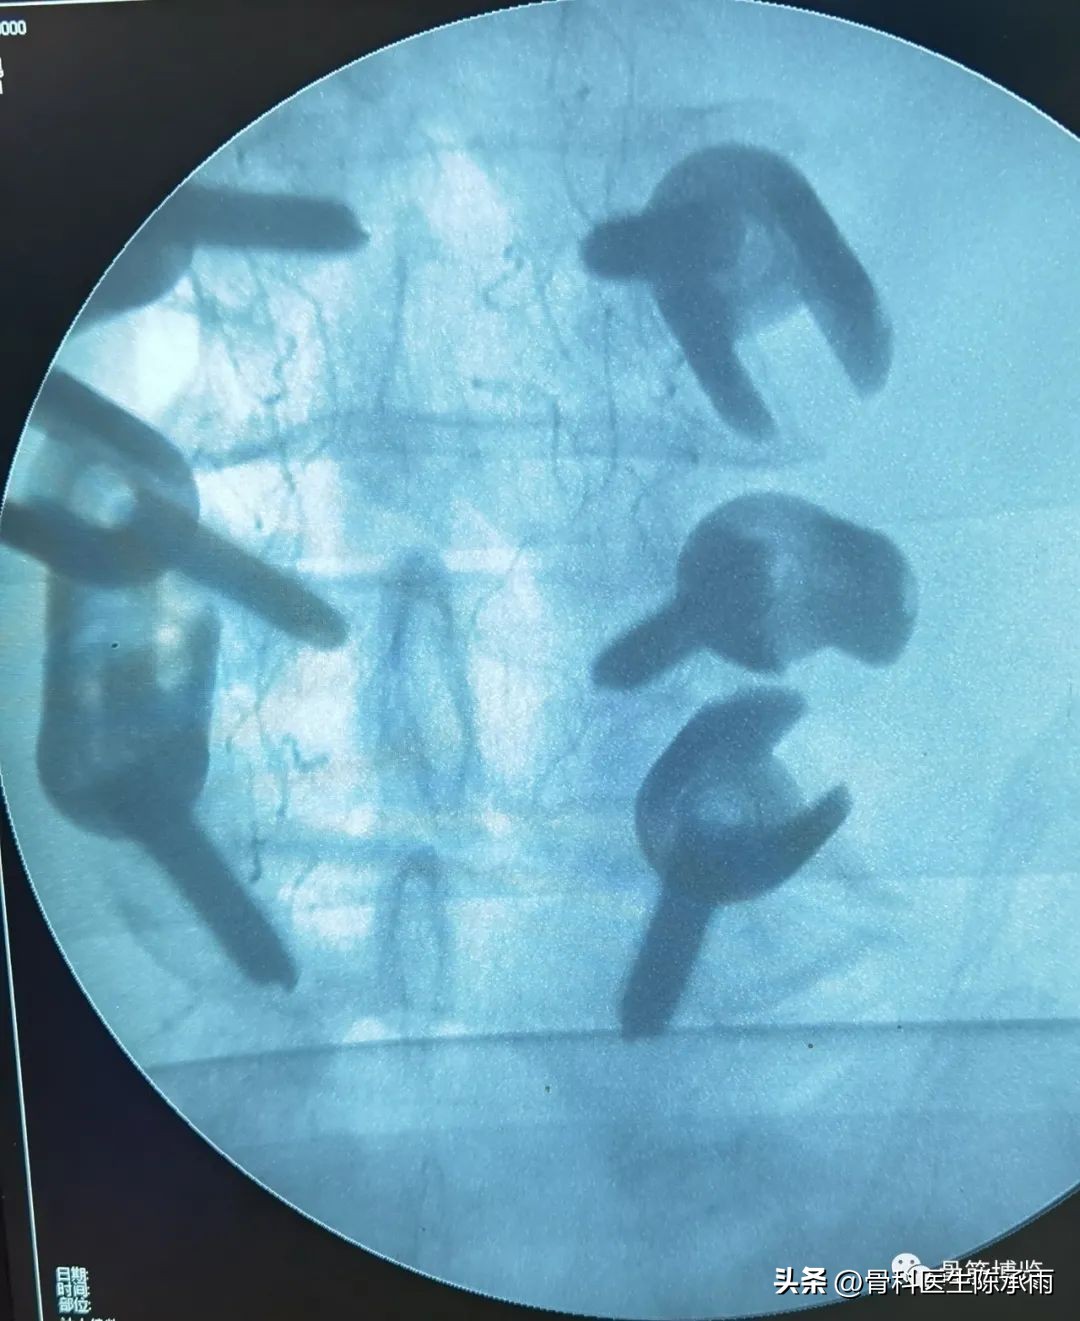

术中C臂